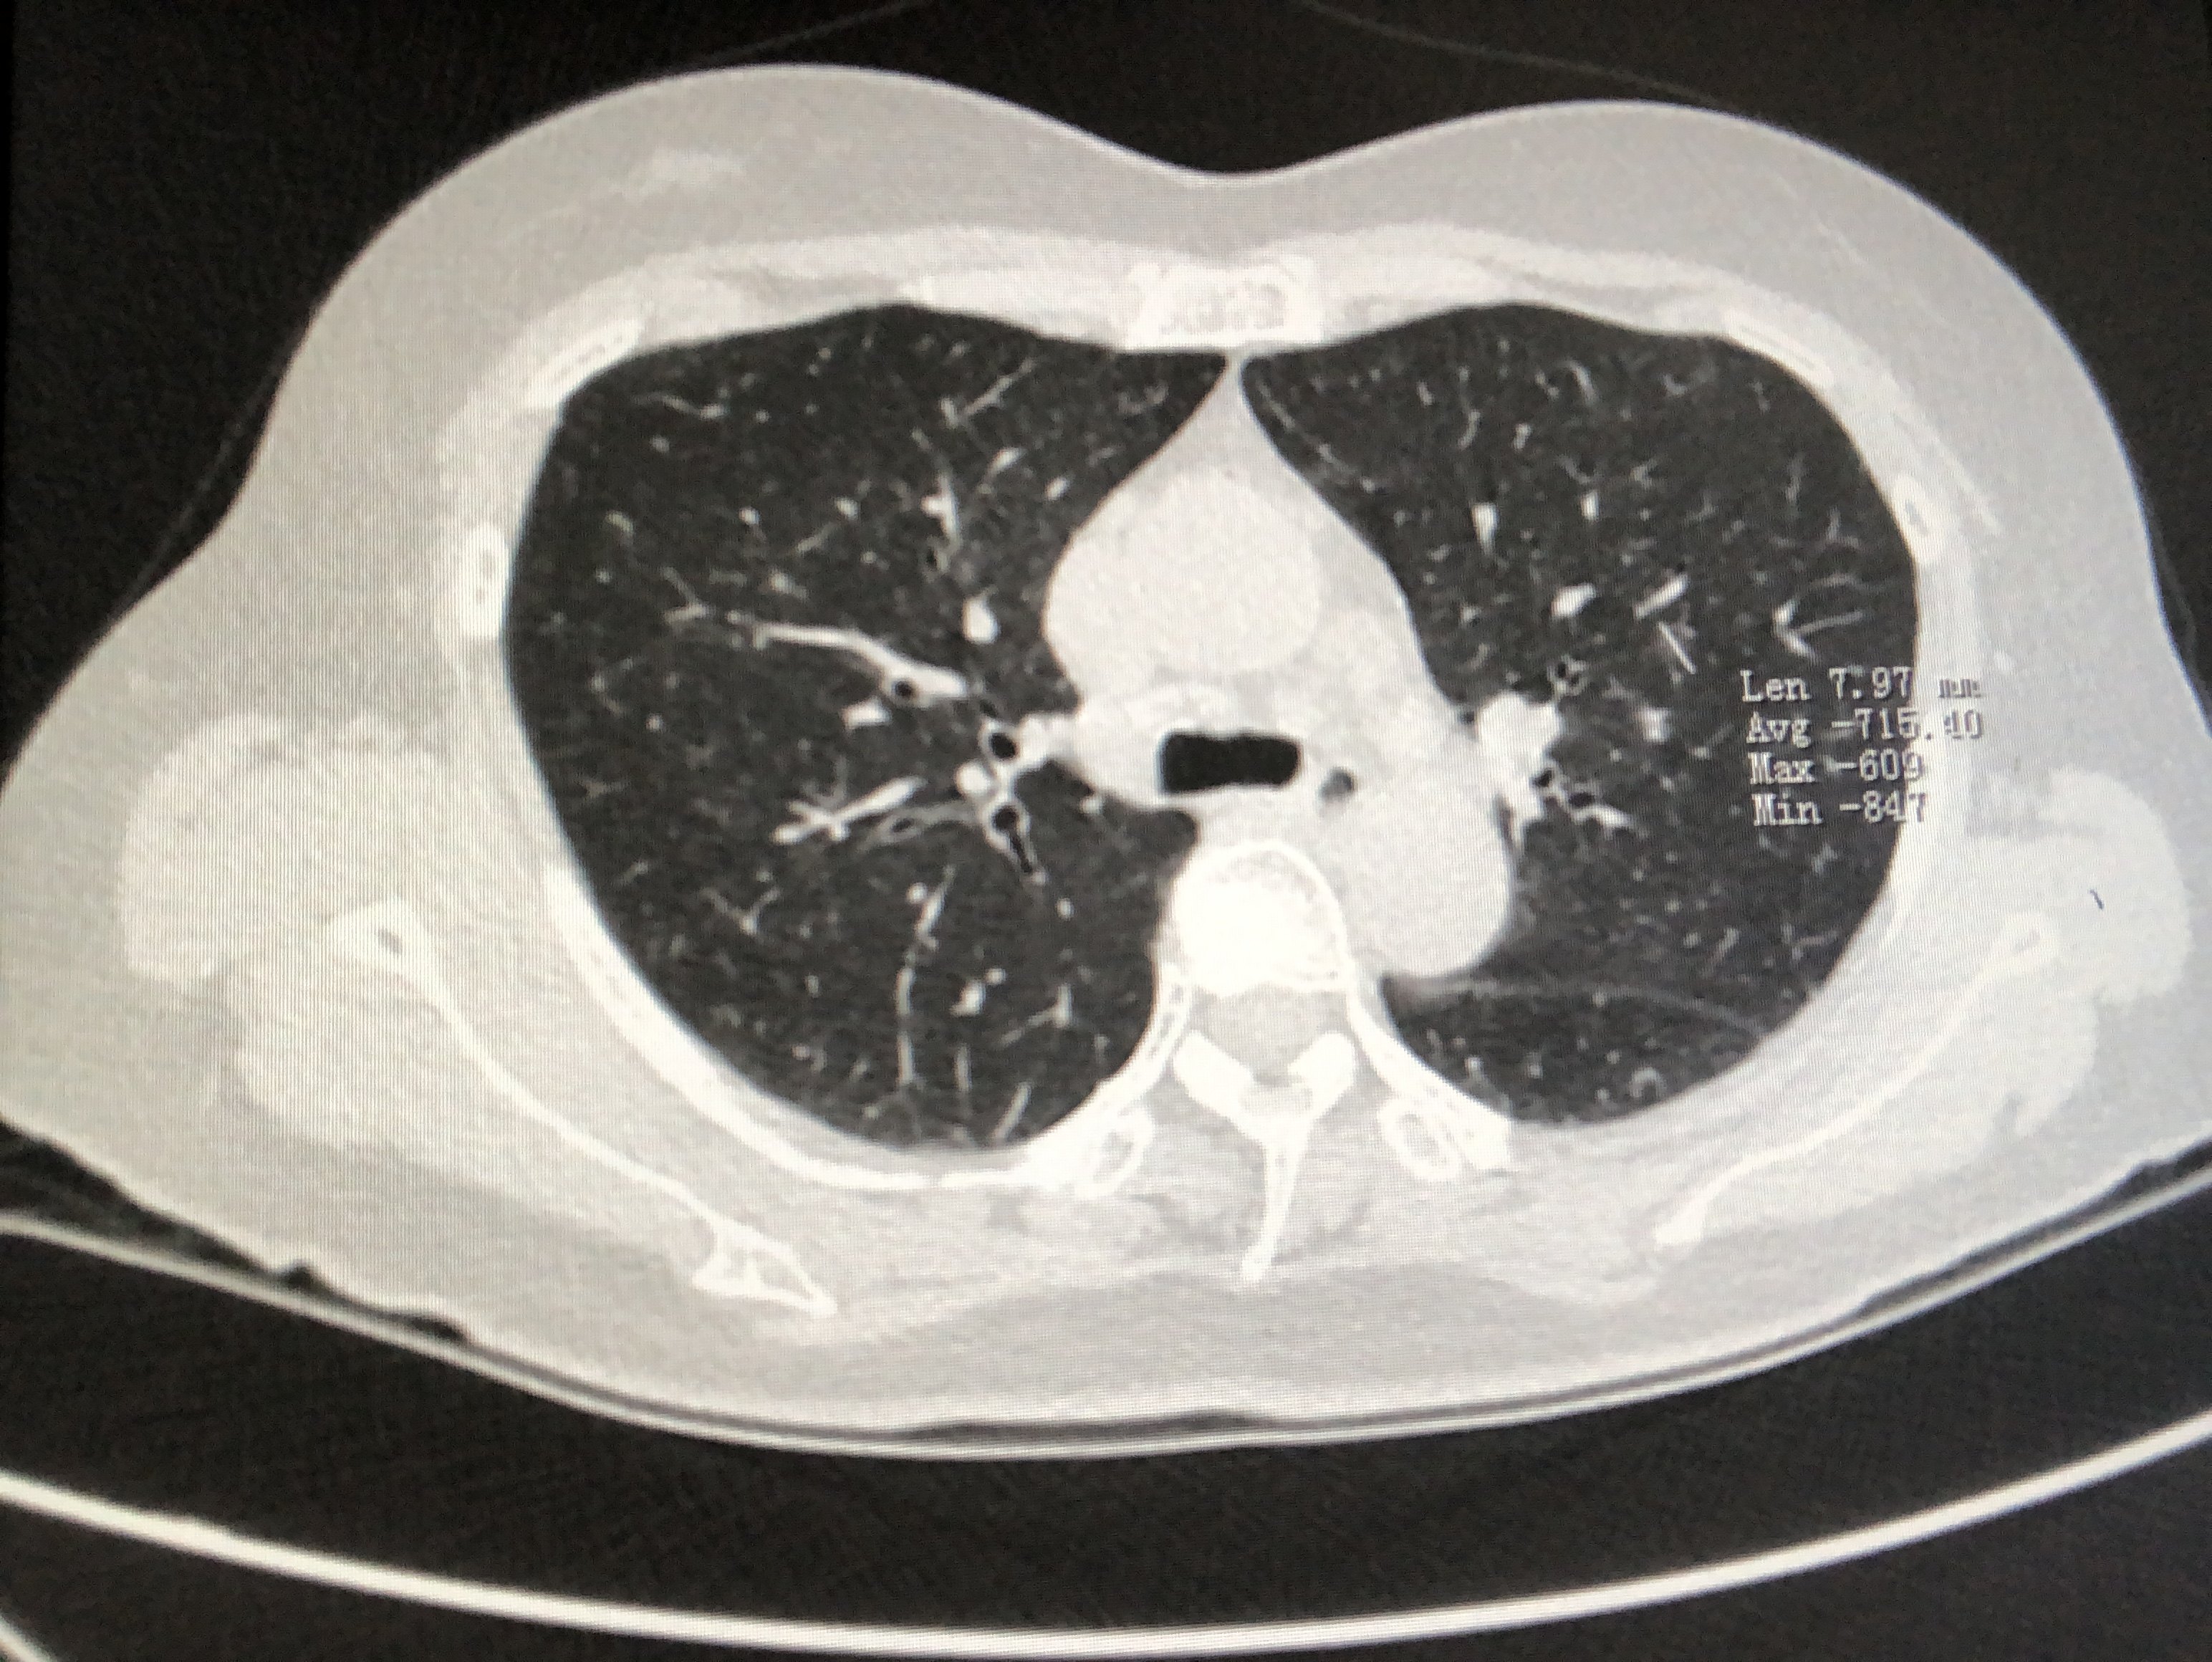

胸部CT

是目前公认的肺部疾病最可靠、最灵敏的影像学检查方法。常规CT扫描灵敏度高但特异性低,多用于筛查高危人群;增强CT扫描可以显示肺结节的基本形态以及结节边缘的细微结构,帮助医生通过相应的检查。数据结果用于确定患者肺结节的密度、边缘、边缘等基本情况。钙化灶与周围环境的关系,进而准确评价肺结节的基本性质。